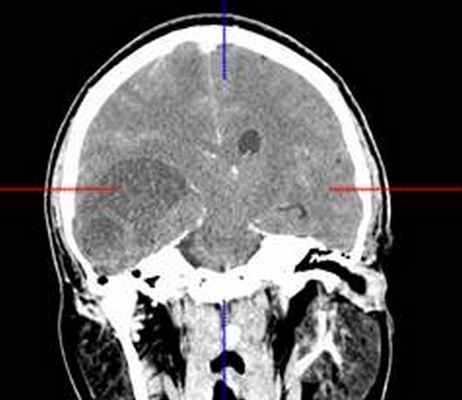

(б) МРТ, постконтрастное Т1-ВИ, аксиальный срез: у того же пациента контрастирования образования не определяется, что является типичным признаком ангиоцентрической глиомы. В смежной с опухолью области часто присутствует участок фокальной кортикальной дисплазии, который должен быть резецирован для предотвращения повторных судорожных приступов. (а) МРТ, Т1-ВИ, аксиальный срез: у шестилетнего ребенка с рефрактерной эпилепсией в структуре коры и субкортикального белого вещества определяется слабовыраженное образование. Обратите внимание на гиперинтенсивные кольцевидные участкичто типично для ангиоцентрической глиомы.

(б) МРТ, Т2-ВИ, корональный срез: у того же пациента определяется повышение интенсивности сигнала от образования, расположенного в области коры и субкортикального белого вещества правой лобной доли. При хирургической резекции была диагностирована ангиоцентрическая глиома. Визуализационные признаки могут напоминать признаки чаще встречающейся ДНЭО.